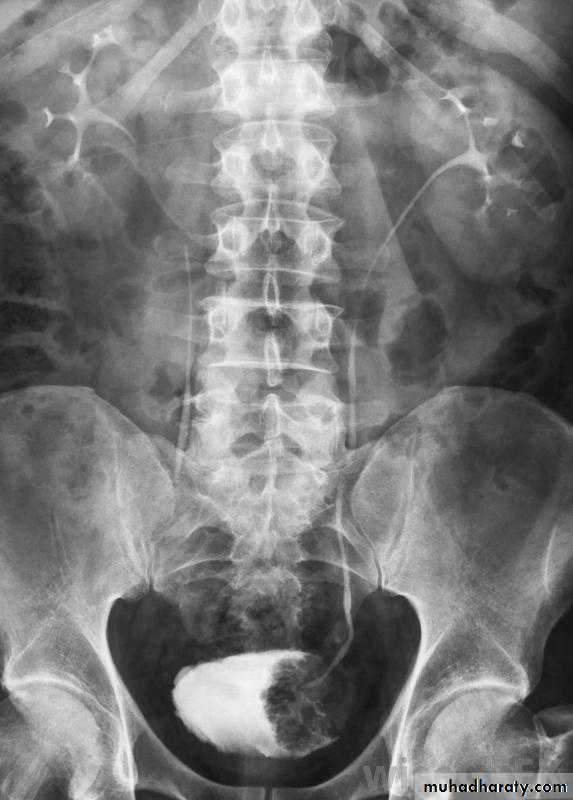

Normal IVU series

Bulb of follys cathter IVU with bilateral mild to moderate degree of HN

RT sided PUJ stenosis & obstruction with RT sided HN